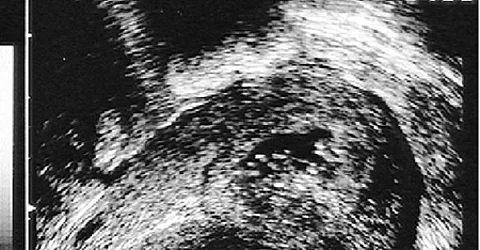

Quelle: Thieme Verlag

Auflösung57-jährige Patientin mit Postmenopausenblutung

Sie haben eine Hysteroskopie + fraktionierter Abrasio und dabei eine Gebärmutterspiegelung und eine schafte Kürettage durchgeführt. Bei der Abrasio wird zuerst der Zervikalkanal und anschließend das Cavum uteri kürettiert. Die Fraktionen werden getrennt asserviert und histologisch beurteilt.